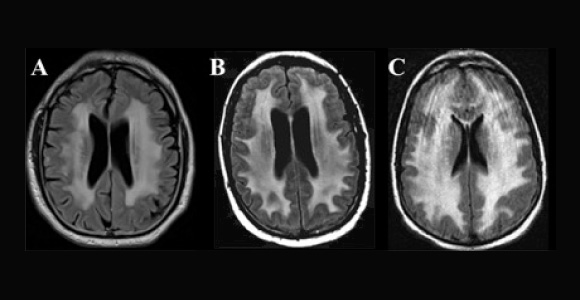

Fazekas grades. Шкала Фазекас мрт. Fazekas классификация мрт. Фазекас 2. 3 Ст. по Fazekas.

Fazekas grades. Лейкоареоз головного мозга мрт. Перивентрикулярный лейкоареоз мрт. Лейкоареоз Фазекас. Лейкоареоз на кт.

Fazekas grades. Лейкоареоз головного мозга мрт. Перивентрикулярный лейкоареоз мрт. Лейкоареоз Фазекас. Лейкоареоз на кт.

Fazekas grades. Лейкоареоз Фазекас. Fazekas 0. Фазекас 3. Фазекас классификация мрт.

Fazekas grades. Лейкоареоз Фазекас. Fazekas 0. Фазекас 3. Фазекас классификация мрт.

Fazekas grades. Fazekas степени мрт. Фазекас 2 мрт. Шкала Фазекас мрт. Лейкоареоз 3 степени по Fazekas.

Fazekas grades. Fazekas степени мрт. Фазекас 2 мрт. Шкала Фазекас мрт. Лейкоареоз 3 степени по Fazekas.

Fazekas grades. Классификация Фазекас. Fazekas мрт. Лейкоареоз степени по Fazekas. Фазекас классификация мрт.

Fazekas grades. Классификация Фазекас. Fazekas мрт. Лейкоареоз степени по Fazekas. Фазекас классификация мрт.

Fazekas grades. Фазекас 2. Fazekas 0. Фазекас 3.

Fazekas grades. Фазекас 2. Fazekas 0. Фазекас 3.